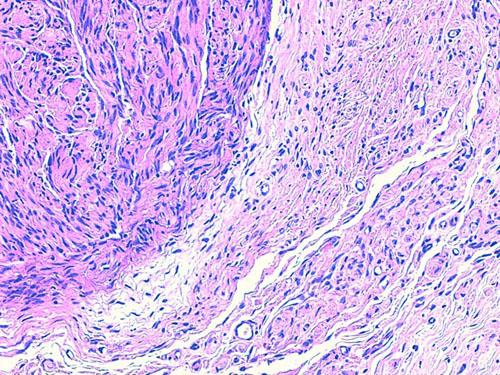

Les nouvelles biopsies mettent en évidence dans le derme profond et l’hypoderme des images identiques de lésions multi-nodulaires, non encapsulées, au sein d’une prolifération cellulaire diffuse de cellules fusiformes. Ces cellules sont peu nombreuses, sans atypie cyto-nucléaire, organisées en faisceaux dans les tissus environnants et les structures annexielles. Ces lésions sont traversées par de nombreuses structures nerveuses périphériques normales. L’épiderme est hyperpigmenté en regard des zones nodulaires (photos 6 à 8).

Photo 7 (HE*200, LAPVSO) : aspects hypo et hyper cellulaires de la tumeur (zones dites « Antoni A et B »)